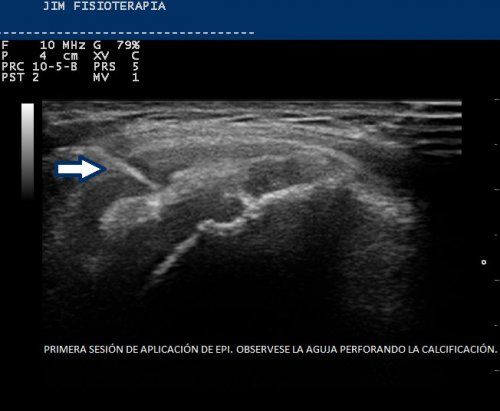

Tratamiento de Tendinosis Calcificada del Supraespinoso con EPI®

Paciente de 60 años de edad con leve sobrepeso, realiza ejercicios de pilates de forma regular y camina diariamente. Es remitida por su traumatólogo con el diagnóstico de tendinitis calcificada del supraespinoso.[...]